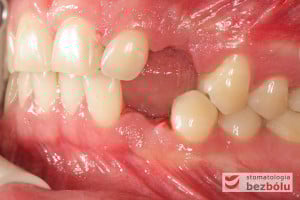

Młody pacjent w wieku lat 28 po wstępnym rozpoznaniu, ze zdiagnozowanym złamaniem kła zarówno górnego jak i dolnego, został skierowany na terapię implantoprotetyczną, prowadzoną przez lekarza dentystę Marcina. W świetle braku możliwości wykonania ekstruzji ortodontycznej i zachowawczego podejścia do leczenia, podjęto decyzję o usunięciu obu zębów, zastosowaniu ułatwiającej gojenie procedury A-PRF i przygotowaniu pacjenta do zabiegu implantologicznego, dodatkowo uzupełnionego o wprowadzenia implantu w miejscu braku zębowego w pEdytujozycji pierwszego przedtrzonowca w szczęce po stronie prawej.

Procedurę chirurgiczną rozpoczęto od sprawdzenia przylegania szablonów do zębów pacjenta oraz znieczulenia miejscowego. W kolejnym kroku, przy pomocy specjalnie przeznaczonego do tego celu zestawu wierteł, wypreparowano krążki dziąsła punktowo odsłaniające kość a następnie poprzez tuleje prowadzące, z najwyższą precyzją, opracowano łoże implantu. Kulminacyjny moment zabiegu, czyli wprowadzenie wszczepów MIS C1 również odbyło się poprzez szablon, gwarantując precyzyjną lokalizację implantów. Zwieńczeniem całej procedury było przyszycie uprzednio wypreparowanych krążków śluzówkowo-okostnowych. Tuż po zabiegu, celem weryfikacji poprawnej pozycji implantów, wykonano zdjęcie ortopantomograficzne. Podczas wizyt kontrolnych, pacjent nie skarżył się na żadne dolegliwości bólowe, nie wystąpił obrzęk, a zreponowane we właściwych miejscach fragmenty dziąsła nie wykazywały oznak martwicy, co świadczyło o ich ponownym ukrwieniu i wgojeniu się. Wszystkie te przesłanki jasno wskazują na skuteczność zastosowania techniki komputerowej nawigacji w implantologii.